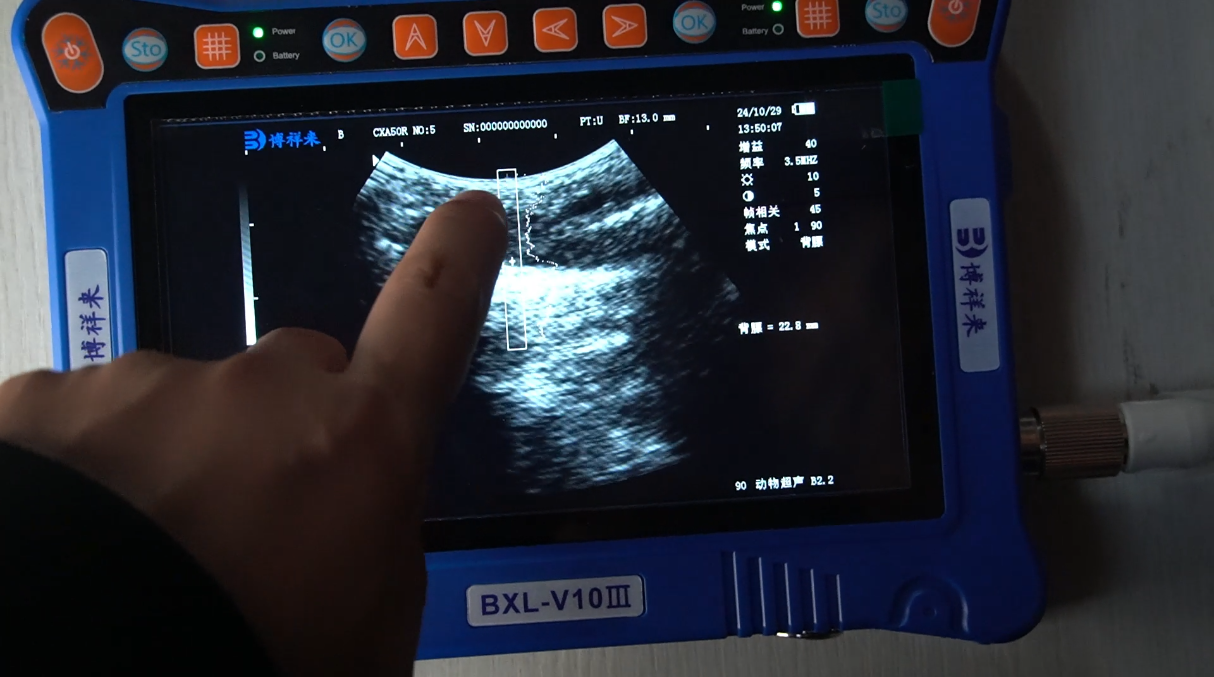

在BXL-V10Ⅲ众多功能中,***引人注目的是一键测背膘的便捷功能。对于需要经常检测动物背膘厚度的养殖场,这一功能极大地提高了工作效率。以下是背膘厚度一键测量的主要好处:

传统的背膘厚度检测通常需要手动操作,耗时且费力,而BXL-V10Ⅲ的一键测背膘功能可以显著缩短检测时间。只需轻触一键,即可完成背膘厚度的测量,使得操作更加简便,大幅减少人力成本。

背膘厚度是一项重要的生产指标,可以反映出动物的营养状况和健康水平。BXL-V10Ⅲ的检测精准度高,能够提供准确的背膘厚度数据,方便养殖人员对动物生长情况进行科学的评估和管理,确保出栏动物的质量达到市场要求。